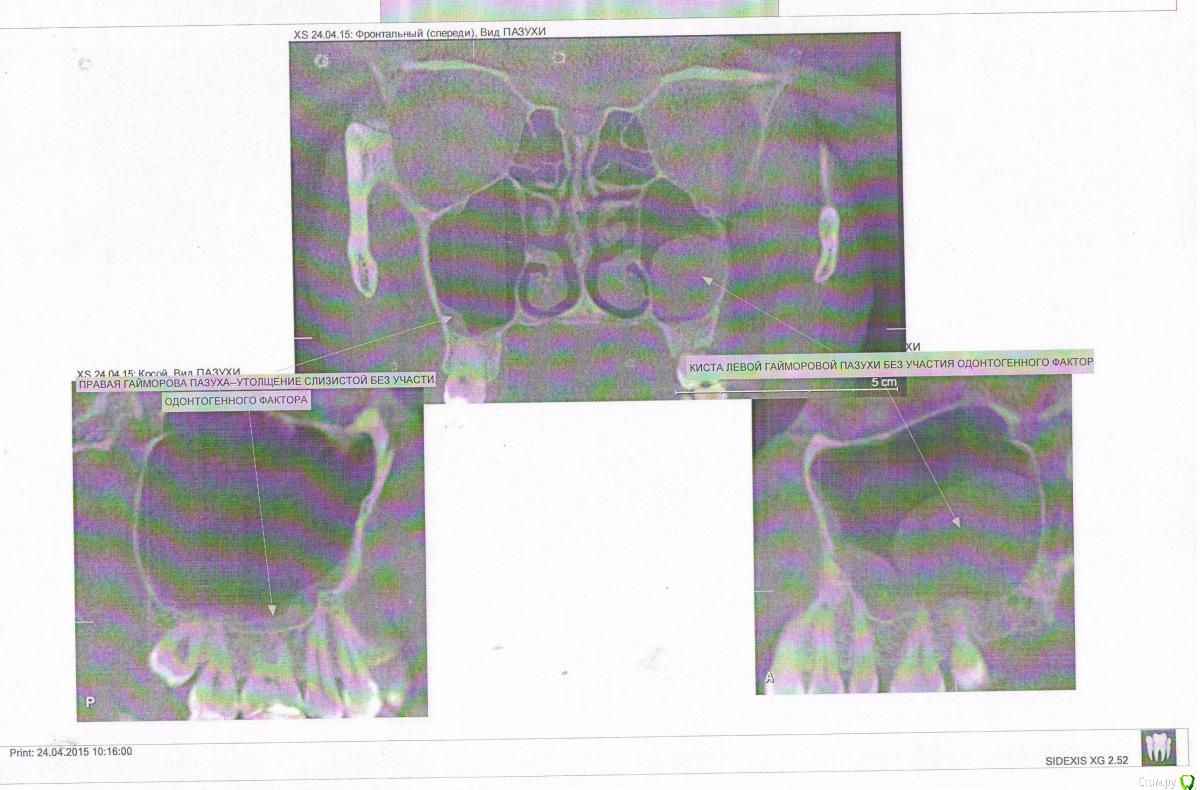

Liso4ka Опубликовано 26 апреля, 2015 Поделиться Опубликовано 26 апреля, 2015 Здравствуйте!Приблизительно с 15.04 у меня начал ныть зуб 21, верхняя 1ка. Ныл по утрам после того, как вставала и принимала вертикальное положение. Поноет, перестанет. В течение дня по несколько раз. Так же реагировал на горячее и немного на холодное. На зубе есть маленькая пломба на стыке с 2кой. по снимкам к пломбе этой претензий тоже нет. и врачи говорят, что она маленькая и не должна по идее "сообщаться" с каналом корневым. Делала снимки - всё ОК. 22,04 пошла к стоматологу в ПК. Она простукивала зуб - боли не было. соседняя депульпированная 2ка тоже безболезненна.Мнение врача - здоровый зуб. Спросила - не болела ли я недавно. И действительно, незадолго до того как начал ныть зуб, у меня закончился длительный насморк (недели 2 точно, с сильной заложенностью, говорила "в нос" очень долго, и даже пропадали некоторые вкусовые ощущения).В общем, пошла я на мРТ, обнаружили кисту гайморовой пазухи левой. Была ли она у меня ранее - не знаю.Так же врач на приеме предложила попробовать поставить антибиотик с лидокаином (линкомицин??) и посмотреть - станет ли легче или нет. Если да, то прийти еще на 1 укол. В общем, вколола антибиотик. Долго он рассасывался, была шишка. После этого укола , В ночь с 23,04 на 24,04 очень сильно начал ныть 1ка, пульсирующая боль. выпила Темпалгин. Отпустило. Но при этом начал зуб реагировать на нажим, постукивания. До этого - НЕ реагировал никак. И при этом реакция на горячее почти прошла! То есть если раньше пила чай горячий - тут же начинал ныть, то сейчас боли совсем почти и нет при питье горячего. Как так? К слову, в месте укола, куда ушло лекарство - слева от крыла носа - при нажиме до сих пор болезненность ощущается. Мог ли укол спровоцировать периодонтит?Может ли киста давать ноющие боли на 1цу?? (вообще сама понимаю, что маловероятно) или если боль при нажиме - то это уже 100% депульпирование?Имеет ли смысл проводить ревизию имеющейся пломбы на 1ке? вскрыть и посмотреть что там под ней? качество скана не очень, конечно (( Ссылка на комментарий